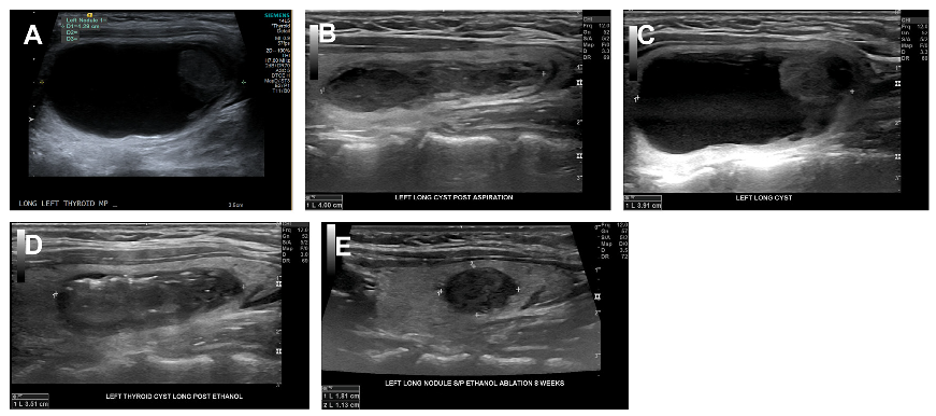

Ethanol Ablation is a well-studied technique for the treatment of symptomatic nodules that are predominantly cystic. Ethanol ablation is a simple outpatient procedure that can significantly shrink cystic thyroid nodules allowing for relief of symptoms and avoidance of surgery.

Ethanol Ablation: A cosmetically bothersome left –sided predominantly cystic nodule (A) Initial ultrasound evaluation (B) following simple aspiration (C) Reaccumulation of cystic fluid, typical following simple aspiration (D) Immediately changes following ethanol ablation (E) sustained benefit of ethanol ablation.